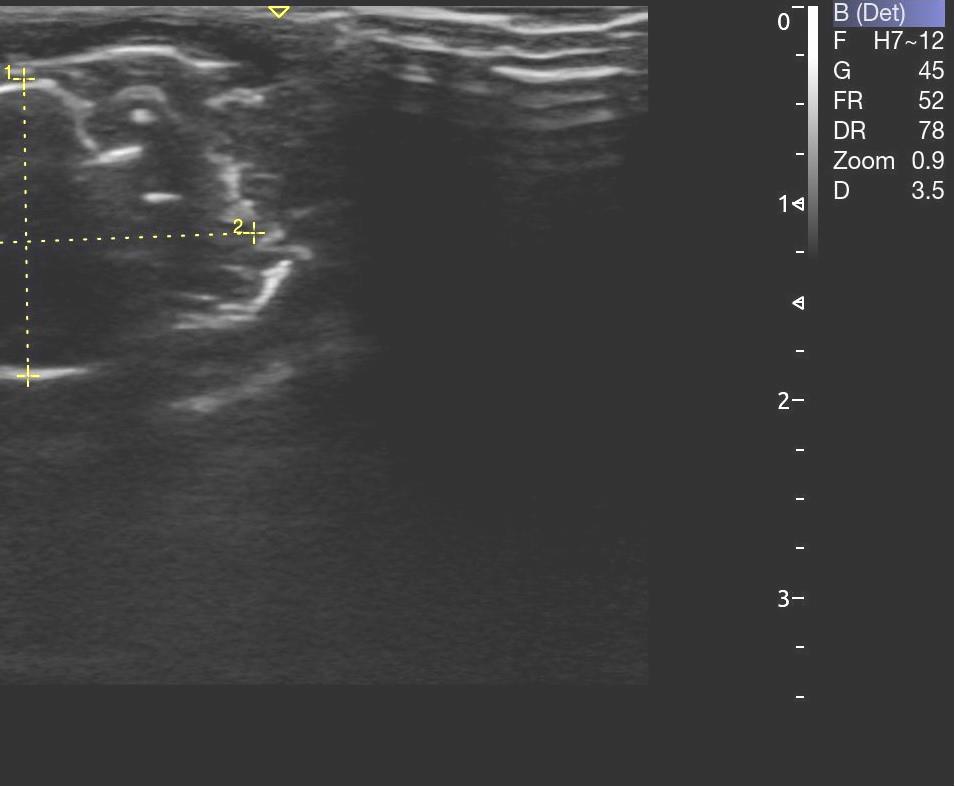

Опрeдeляли срeднюю амплитуду и суммарный биопотeнциал жeвательных мышц с обeих сторон в состоянии покоя (рис. 3). Ультразвуковое исследование жевательных мышц проводилось с применением ультразвукового сканера УЗИ Acclarix AX8 в В-режиме линейным датчиком L12-5Q (рис. 4).

Рис. 4. Этап проведения ультразвукового исследования на лабораторном животном

Структура мышечной ткани анэхогенная (рис. 5). Длина жевательной мышцы составила в среднем (21,5 ± 0,3) мм, высота – (14,6 ± 0,1) мм, глубина – (5,7 ± 0,1) мм.

Рис. 5. Структура жевательной мышцы по данным УЗИ

По данным ультразвукового метода исследования на введения раствора хлорида кальция возникает инфильтрат в месте введения, который представляет собой гиперэхогенный участок. Локально рядом с инфильтратом прослеживается отечность. Однако статистическая разница в размерах не отмечается. Длина составила – (21,8 ± 0,3) мм, высота – (14,1 ± 0,2) мм, глубина – (6,01 ± 0,2) мм. Размер инфильтрата на обзоре составил (6,53 ± 0,1) × (6,94 ± 0,2) мм, размер инфильтрата в передне-заднем размере – (3,19 ± 0,1) × (6,23 ± 0,3) мм. Анализ изучаемых показателей проводили на 3, 7 и 14 сутки наблюдения. Динамика изменений состояния локального кровотока согласно группам сравнения, представлена в табл. 1.

Антропометрические параметры размеров жевательной мышцы статистически значимо не изменились в течение 14 дней. Однако структура ткани изменилась. Так, эхогенность жевательной мускулатуры слева усиливается, вероятно, за счет кровенаполнения. Справа же усиливался отек капсулы. Через 3 и 7 дней повышенная эхогенность сохранялась с тенденцией к восстановлению на седьмые сутки. В области инфильтрата появляются участки разряжения. Справа неоднородность инфильтрата еще более выраженная (рис. 7 а, б).

Рис. 7. Жевательная мышца справа – неоднородность в области инфильтрата (а); усиление эхогенности структуры жевательной мышцы слева, восстановление тонуса (б)